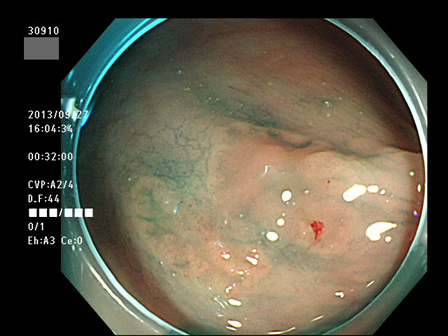

上記100名より抽出した平坦・陥凹型腺腫(=癌化の危険が高いが見落としやすい病変)の内視鏡写真

30901 30902 30904 30907 30909 30910 30912 30913 30915 30919 30920 30921